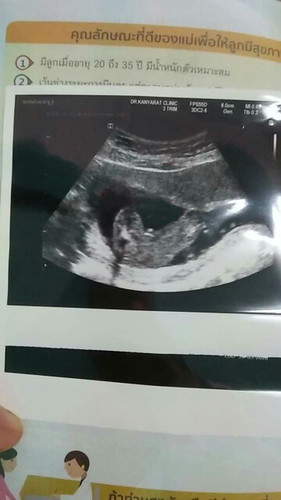

ชายค่ะ บ้านนี้ก็ท่านี้เลย เห็นแบบนี้เลยค่ะ

เหมือนจะเป็นผู้ชายเลยนะแม่

เหมือนจู๋น้องเลยเเม่😂

Boy ใช่มั้ยแม่ ยินดีด้วยค่ะ

น่าจะชายค่ะแม่

คิดว่าชายนะคะ